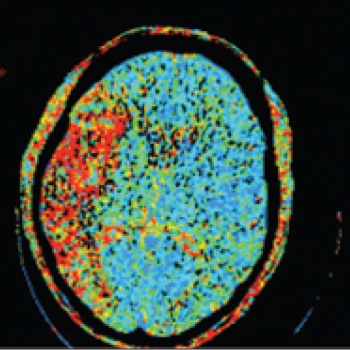

See Figures 1(i)-3(ii) for images of a successful endovascular therapy case.

Figure 1 (i): this and Figure 1(ii) show axial and coronal CT angiogram identifying proximal right MCA (M1) occlusion(click to enlarge)